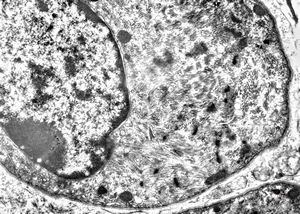

M,2y. | myopathy - regenerating muscle cell